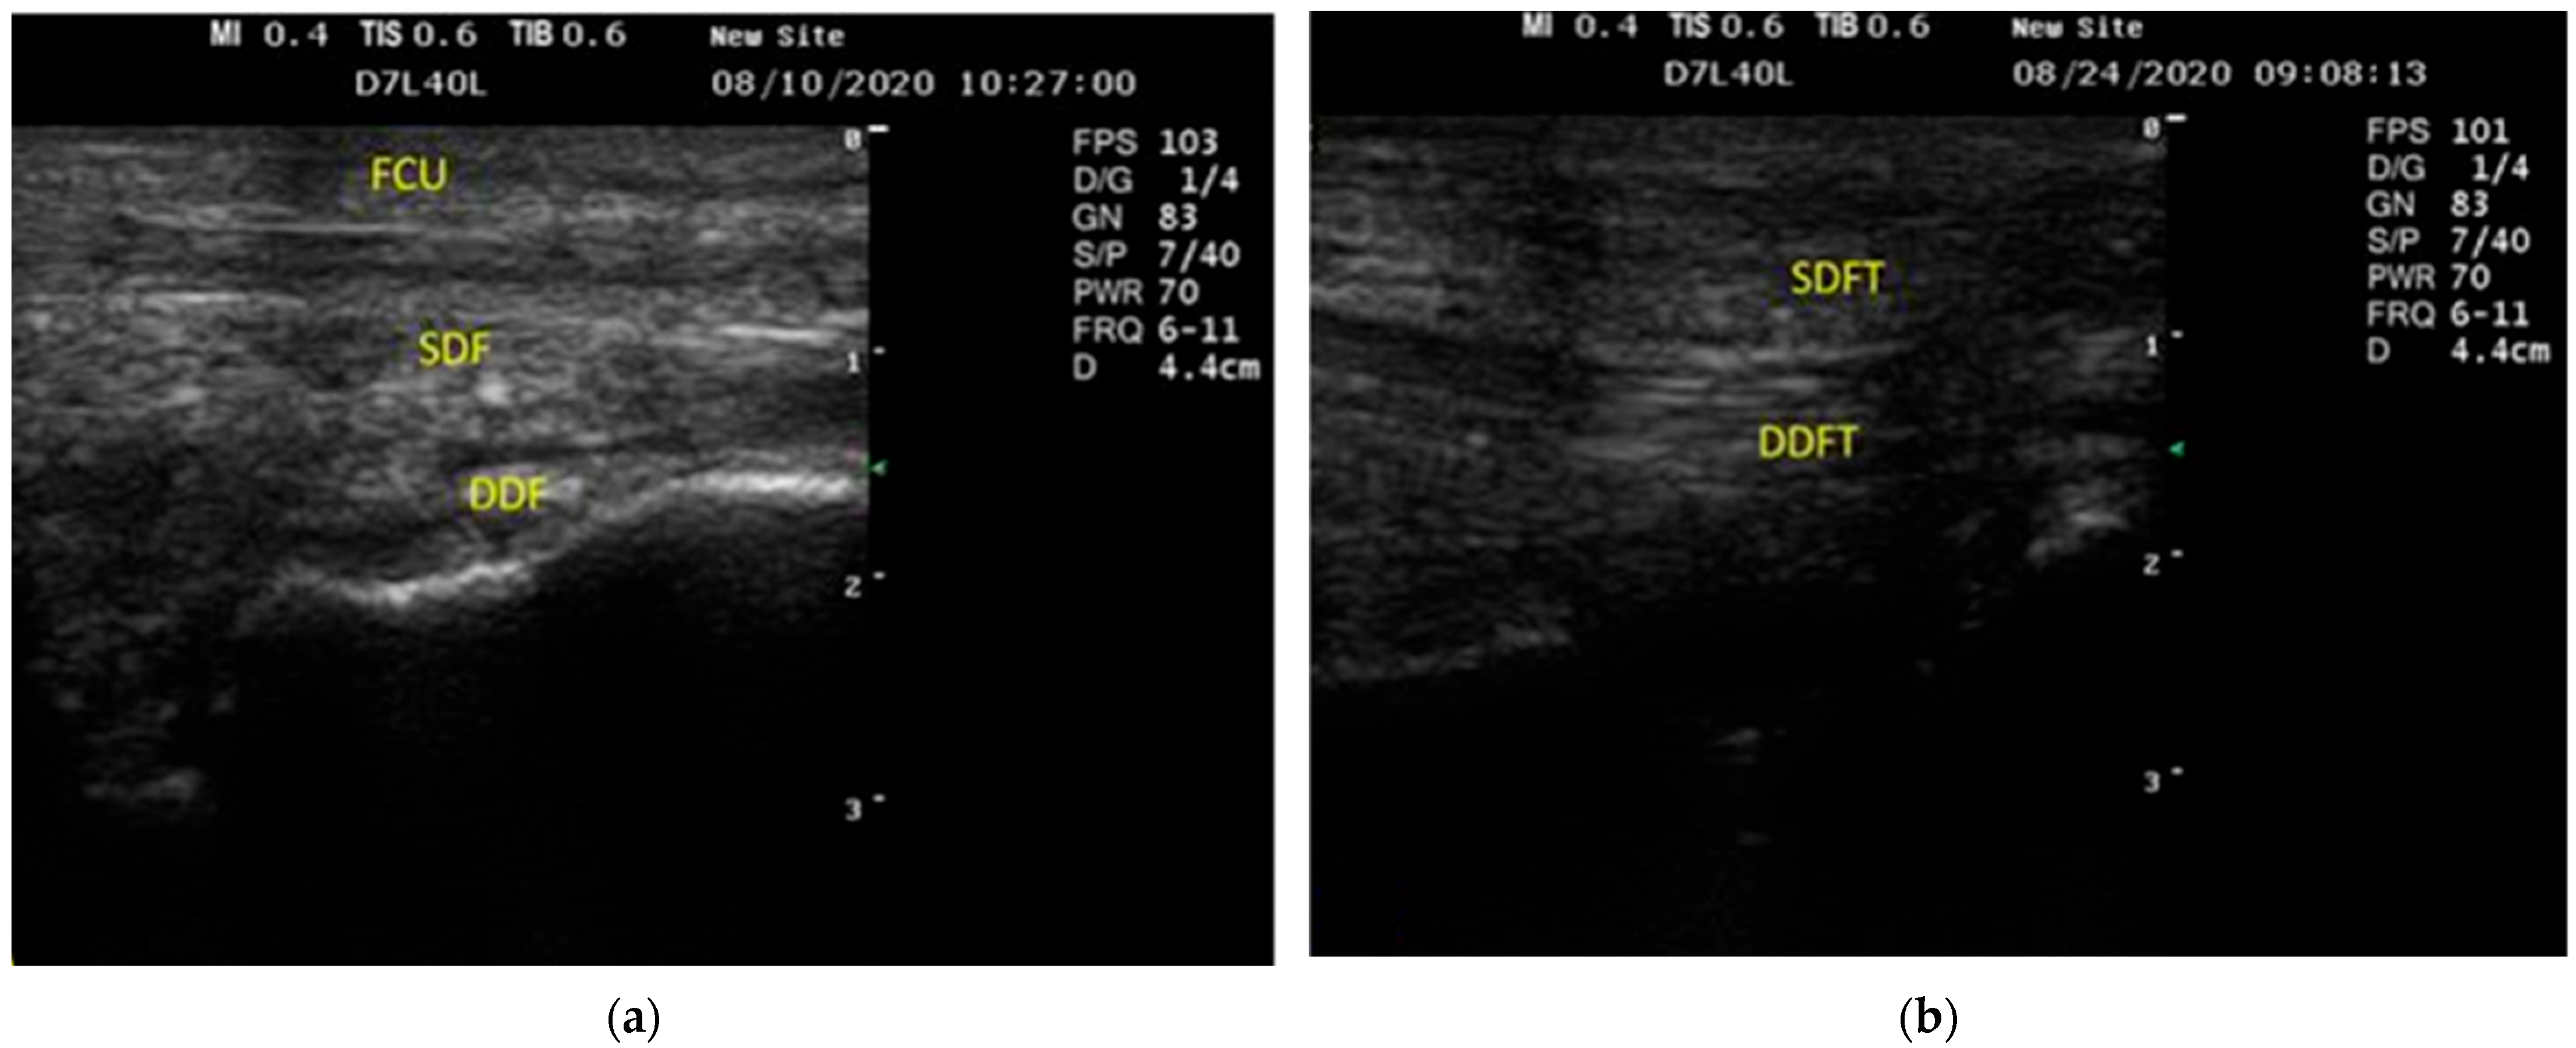

3.1. US Findings